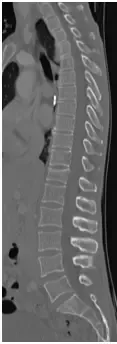

48 yo Female had a sledding injury when she landed on her buttocks following a fall. She felt a “pop” and immediate back pain. She was able to walk briefly, but quickly incapacitated by pain. Her examination suggested an injury to the lower thoracic spine. She was neurologically intact. She had uncontrolled pain. X Rays and CT scan of the patient showed fracture of T12 vertebral body.